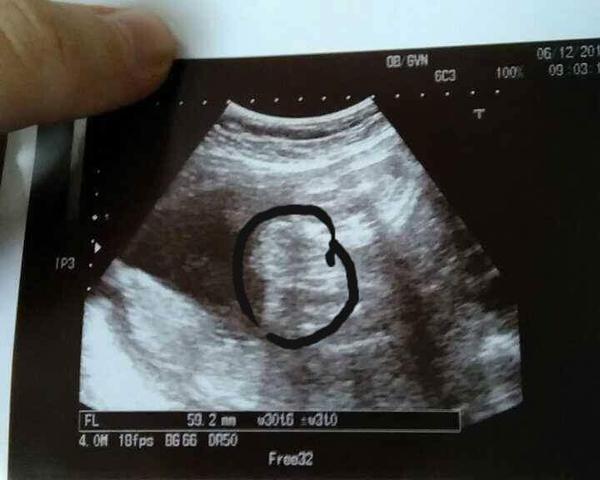

Je to holčička nebo chlapeček? Foto ultrazvuku

Ahoj maminky a budoucí maminky 😉 Prosím, poradila byste mi některá, co vidíte na fotce z ultrazvuku ve 20. týdnu za pohlaví? Určitě jste foteček viděly už mraky, proto vás žádám o radu...Nechci nikoho ovlivnit, proto svůj tip řeknu později 🙂 Děkuju moc!!!

@nikyta159: no ja sem toho zdarny priklad :D do 23tt kluk pak uz jen holka a mam ji :-* doufam ze se ted nesekla !!! @mariejosef: podle me jasna holka 🙂

@mariejosef podle mě taky jasná holka, ale nejsem doktor...jsem fakt zvědavá, co se v ti v.tom bříšku skrývá.. 🙂

@nikyta159 to je jako pohled ze zadu od prdelky?

@mariejosef no jakoby zespodu asi 😀 ja se v tom taky moc nevyznam...me stačí, že mi doktor dal fotku a řekl, ze to jsou koule 😀